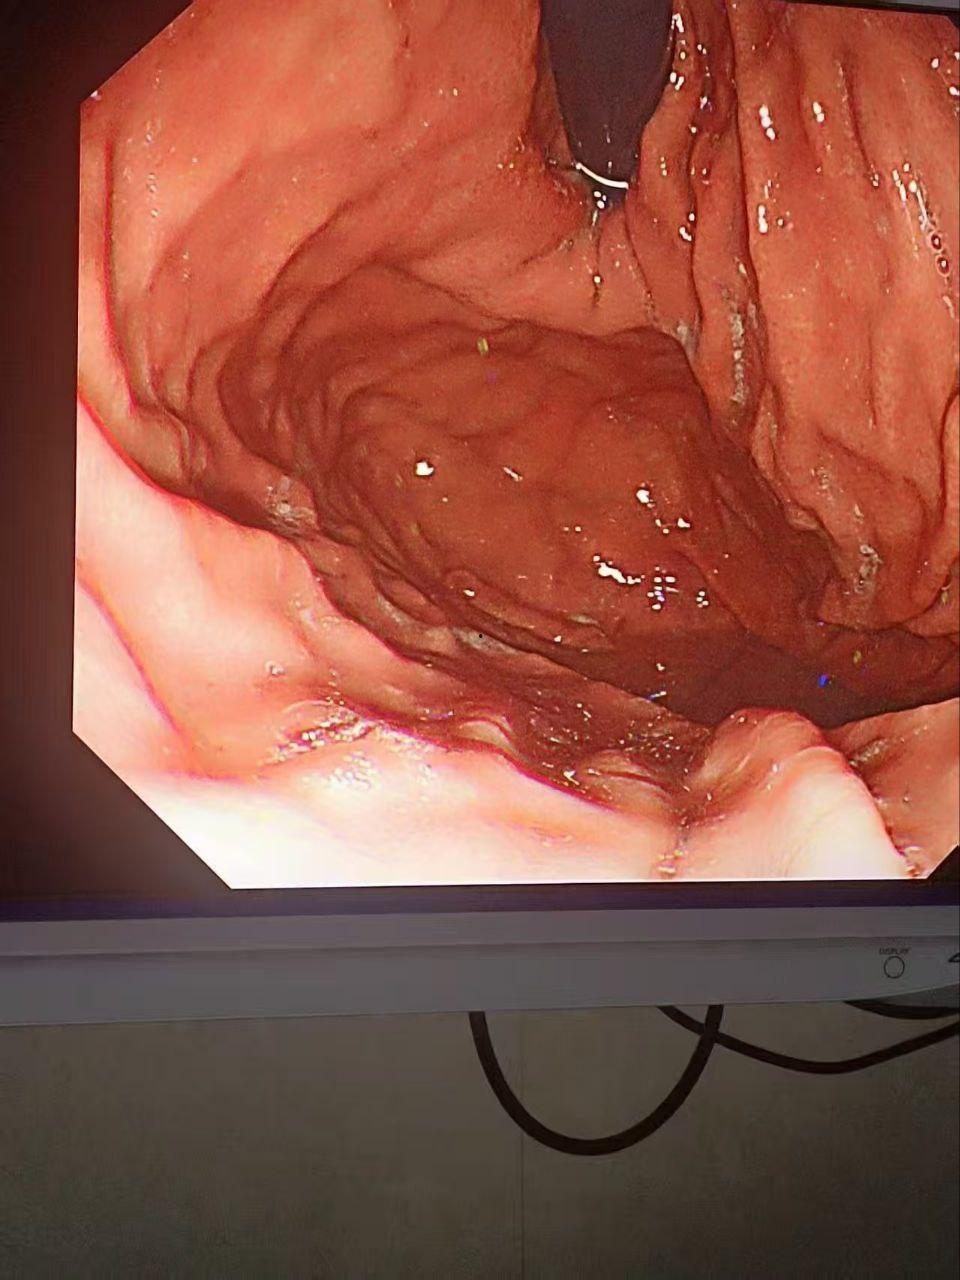

金主酒吧消费巨款,陪酒女为博金主一笑,酒后拳交,玩大了,金主爸爸手上戒指卡里面!

金主酒吧消费巨款,陪酒女为博金主一笑,脑子一热跟金主玩酒后抠屁眼,现场有姐妹看着,但不料还是玩大了,金主爸爸狂抠,不料戒指掉进屁股里找不到了,事后才发现顺着小肠进去了,你们有钱人玩的真花呀。